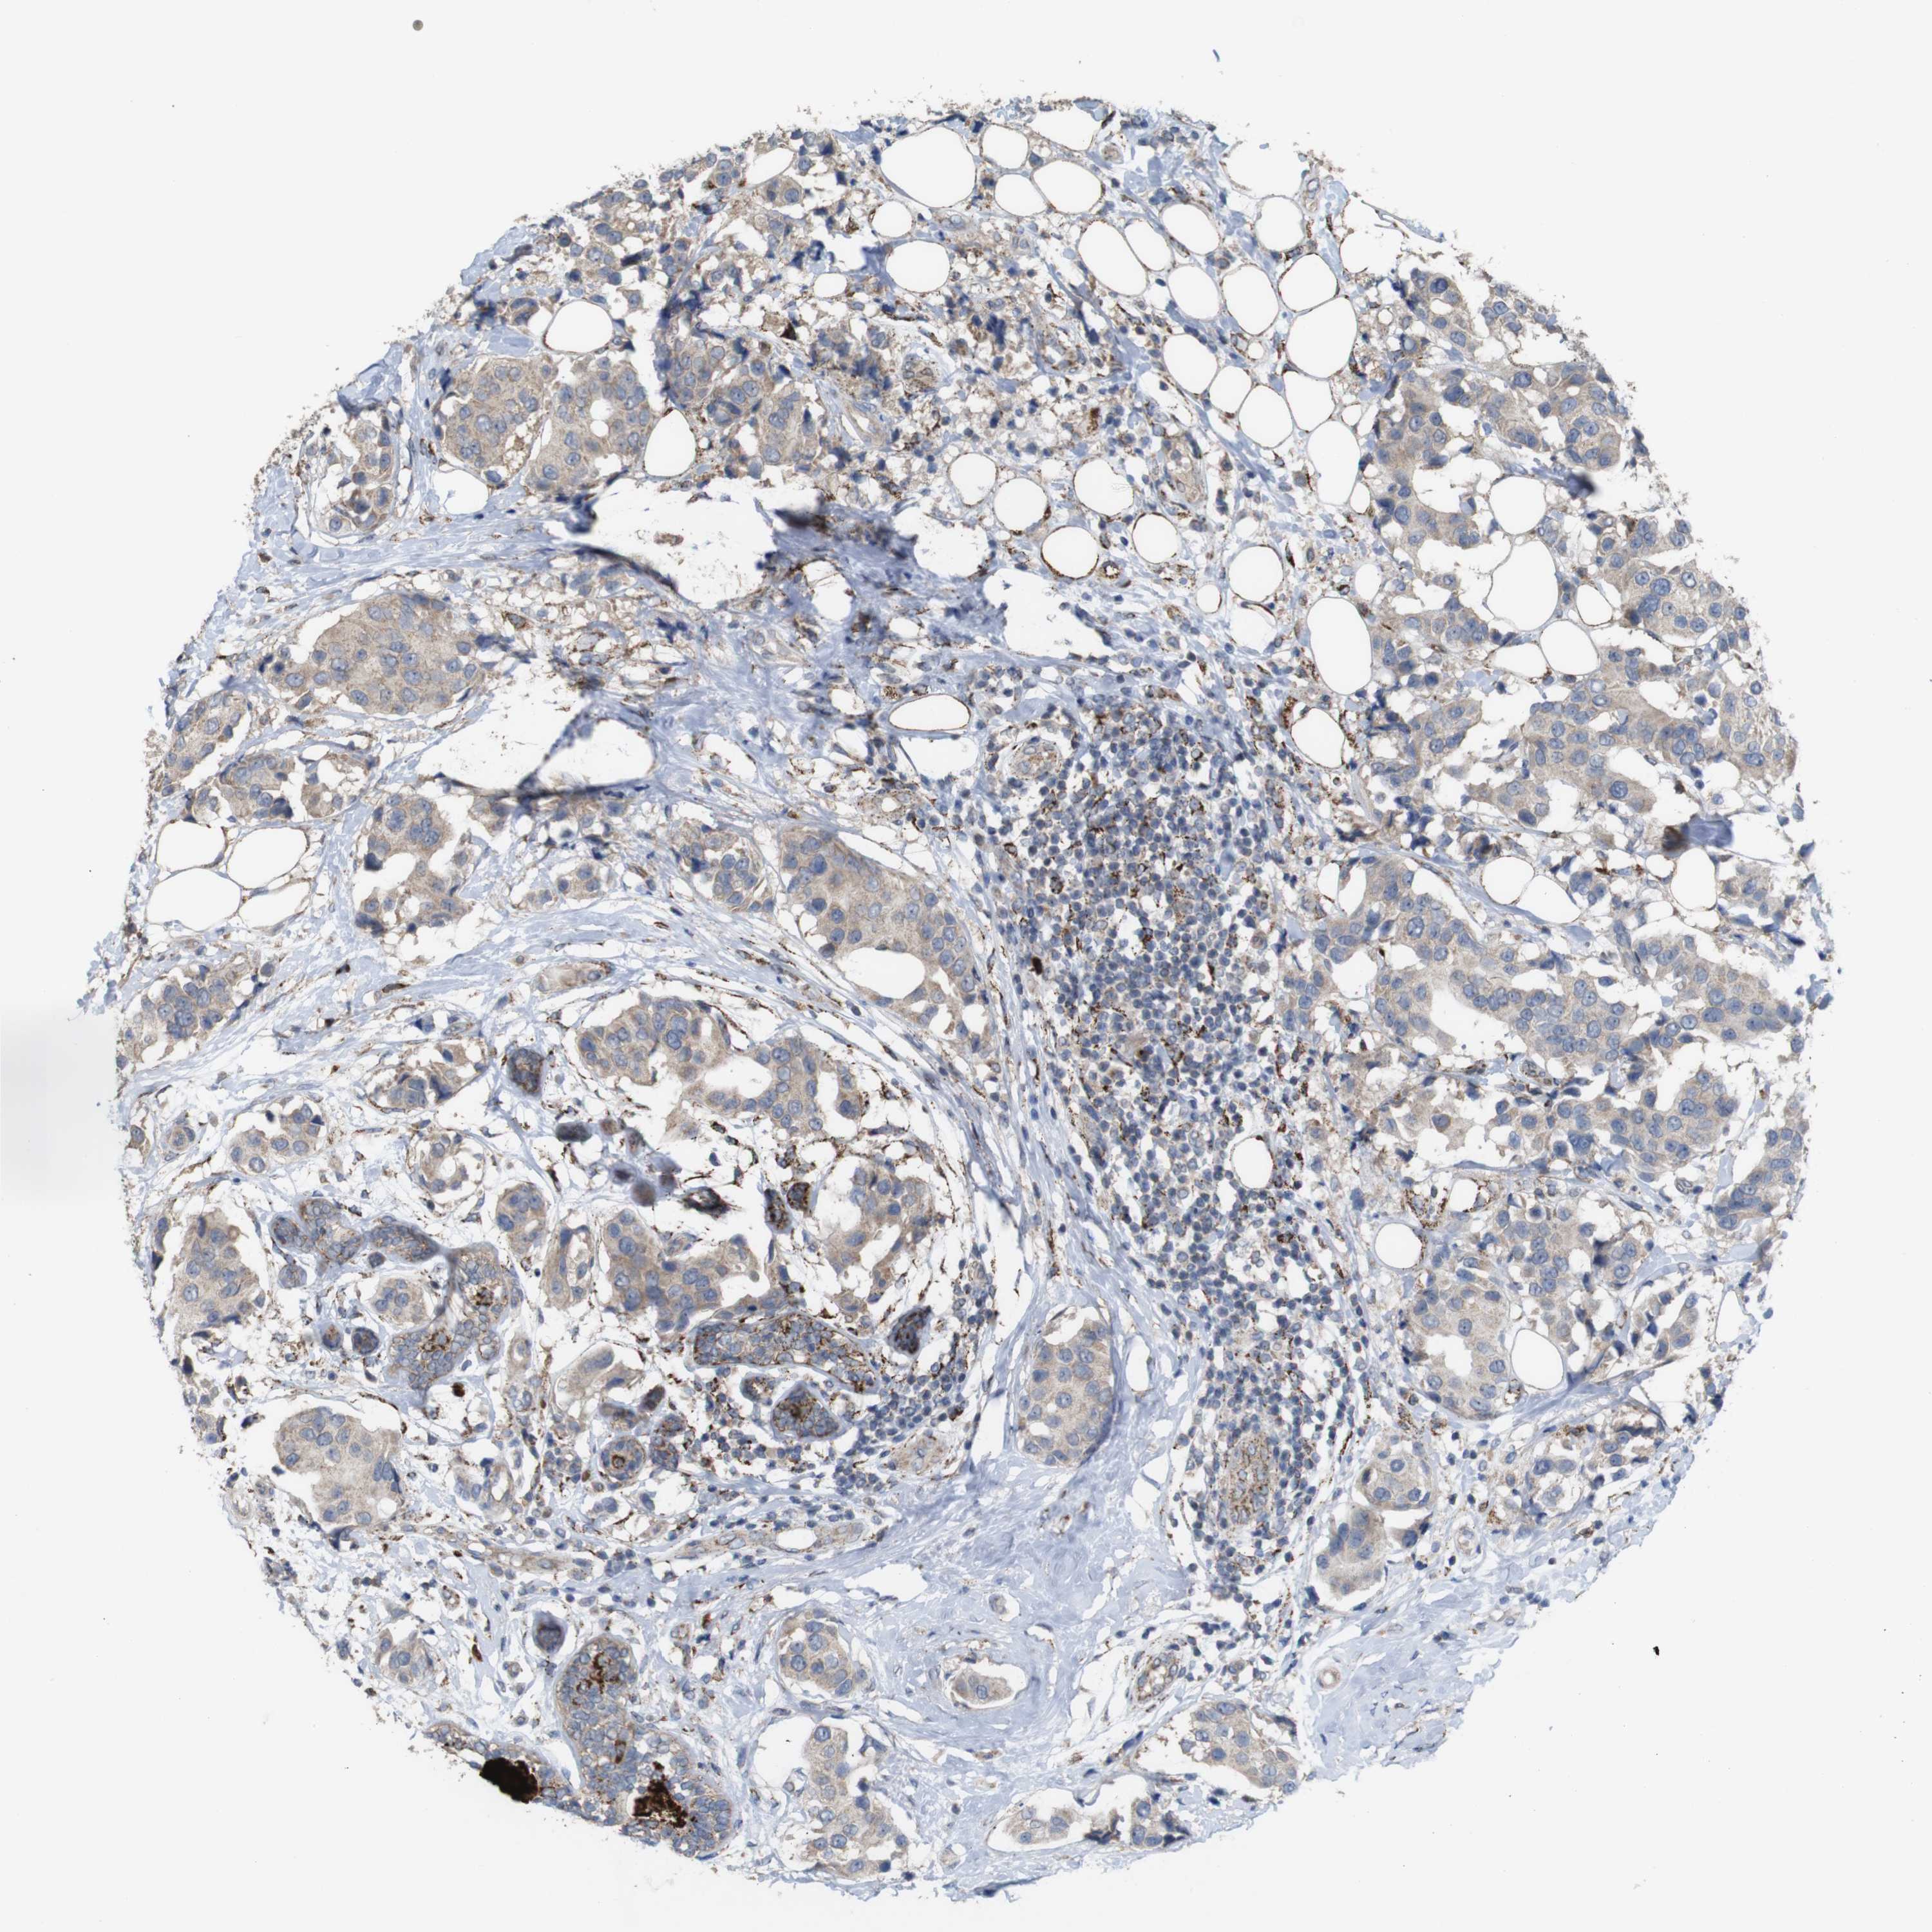

CANCER BREAST CANCER Show tissue menu

BRCA TCGA BRCA VALIDATION PROTEIN EXPRESSION